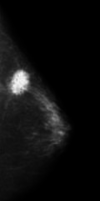

Imagen con resolución 1024Mp. Fuente: Proyecto en desarrollo, División de Ciencias Exactas y Naturales de la UNISON.

Figura 9: Imagen con resolución 1024Mp. Fuente: Proyecto en desarrollo, División de Ciencias Exactas y Naturales de la UNISON.

A continuación se presentan los resultados proporcionados por K-Means de la segmentación de la Figura 9 que tiene un tamaño de pixeles, por lo tanto una matriz de tamaño , dando distintos valores de y con centroides iniciales arbitrarios, esto es, aplicando el algoritmo K-Means sin hacer alguna selección especial de los centroides iniciales. Un preprocesamiento (selección de centroides iniciales de manera adecuada al problema) como el que se presenta en [14] fue utilizado posteriormente para segmentar la misma imagen, obteniendose resultados mucho más significativos que utilizando el algoritmo sin él, como se puede ver en la Figura 11.

Figura 10: Segmentación de mamografía con K-Means con centroides iniciales arbitrarios. Fuente: Elaboración propia.

Las segmentaciones obtenidas en la Figura10 significan, que se buscan dentro de la mamografía, tres y cuatro tonalidades diferentes en la escala de grises. Por ejemplo en la Figura 10a solo se aprecia el contorno color blanco de la mamografía y dos tonalidades diferentes en el fondo. En la Figura 10b se aprecia que dentro de la mamografía hay cuatro tonalidades diferentes, blanco, negro y dos tonalidades de tipo diferente de gris, sin embargo, esto no proporciona información relevante, ya que se busca la existencia de microcalcificaciones dentro de la mamografía. Por tal motivo, es necesario realizar el preprocesamiento descrito en [14], que realice una elección adecuada de los centroides iniciales, para así hacer evidente la existencia de microcalcificaciones dentro de la mamografía.